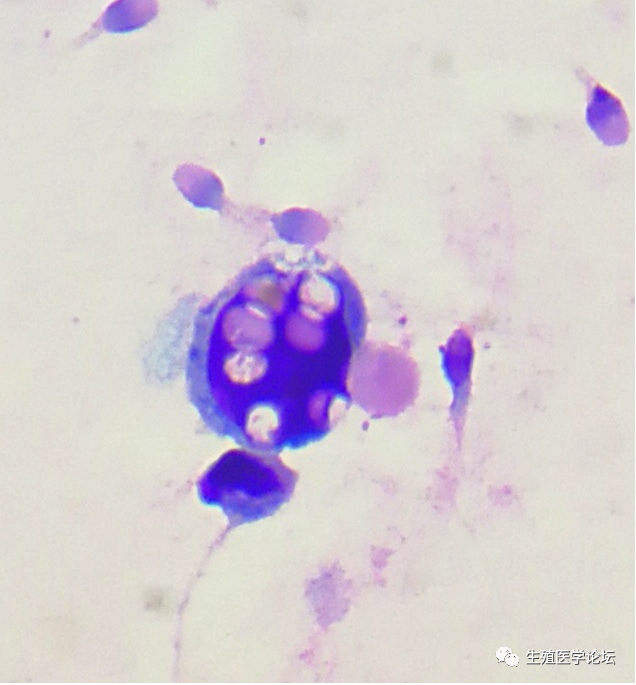

如果生精细胞在某个阶段出现堆积、比例增高,可大致判断生精阻滞的阶段,其中初级精母细胞阶段最为常见,精子细胞阶段次之,精原细胞阶段少见。生精细胞不仅可以表现为数量和比例异常,还可以表现为形态异常,其形态特征主要以凋亡和胀亡为主,凋亡主要表现为细胞核固缩、边聚、突出、凋亡小体等,胀亡表现为细胞核膨胀、均质化、胞膜崩解等。细胞凋亡和胀亡代表两种不同的细胞死亡方式。根据生精细胞的异常脱落,对探索不育症的病因及发生机制有着重要价值,并可作为疗效观察和判断预后的重要指标。精子细胞阶段分化不良,多核、凋亡

精液中其他有形成分包括支持细胞、白细胞、上皮细胞、结晶及病原微生物等,所有有形成分的检出都有其临床意义。支持细胞是唯一与生精细胞接触的细胞,支持细胞具有支持、营养、释放、分泌、吞噬等多种功能,为生精细胞的分化和发育成熟提供了一个特殊的微环境,为精子的发育提供了必要的环境基础。在健康精液中支持细胞无或极少脱落,在非梗阻性无精子症较为常见,如精液中仅检出支持细胞,未见生精细胞,考虑为支持细胞综合症的可能。精液中的中性粒细胞和单核/巨噬细胞

精液中出现前列腺上皮、精囊腺上皮及附睾上皮细胞则可提示附性腺的功能损伤;检出线索细胞考虑来自包皮垢或体外射精,建议双方治疗;生精细胞内包涵体的检出考虑病毒感染的可能,应给予重视;精液中大量残渣与支持细胞的吞噬功能下降有关,不应忽视。精液中的线索细胞

生精细胞内的包涵体